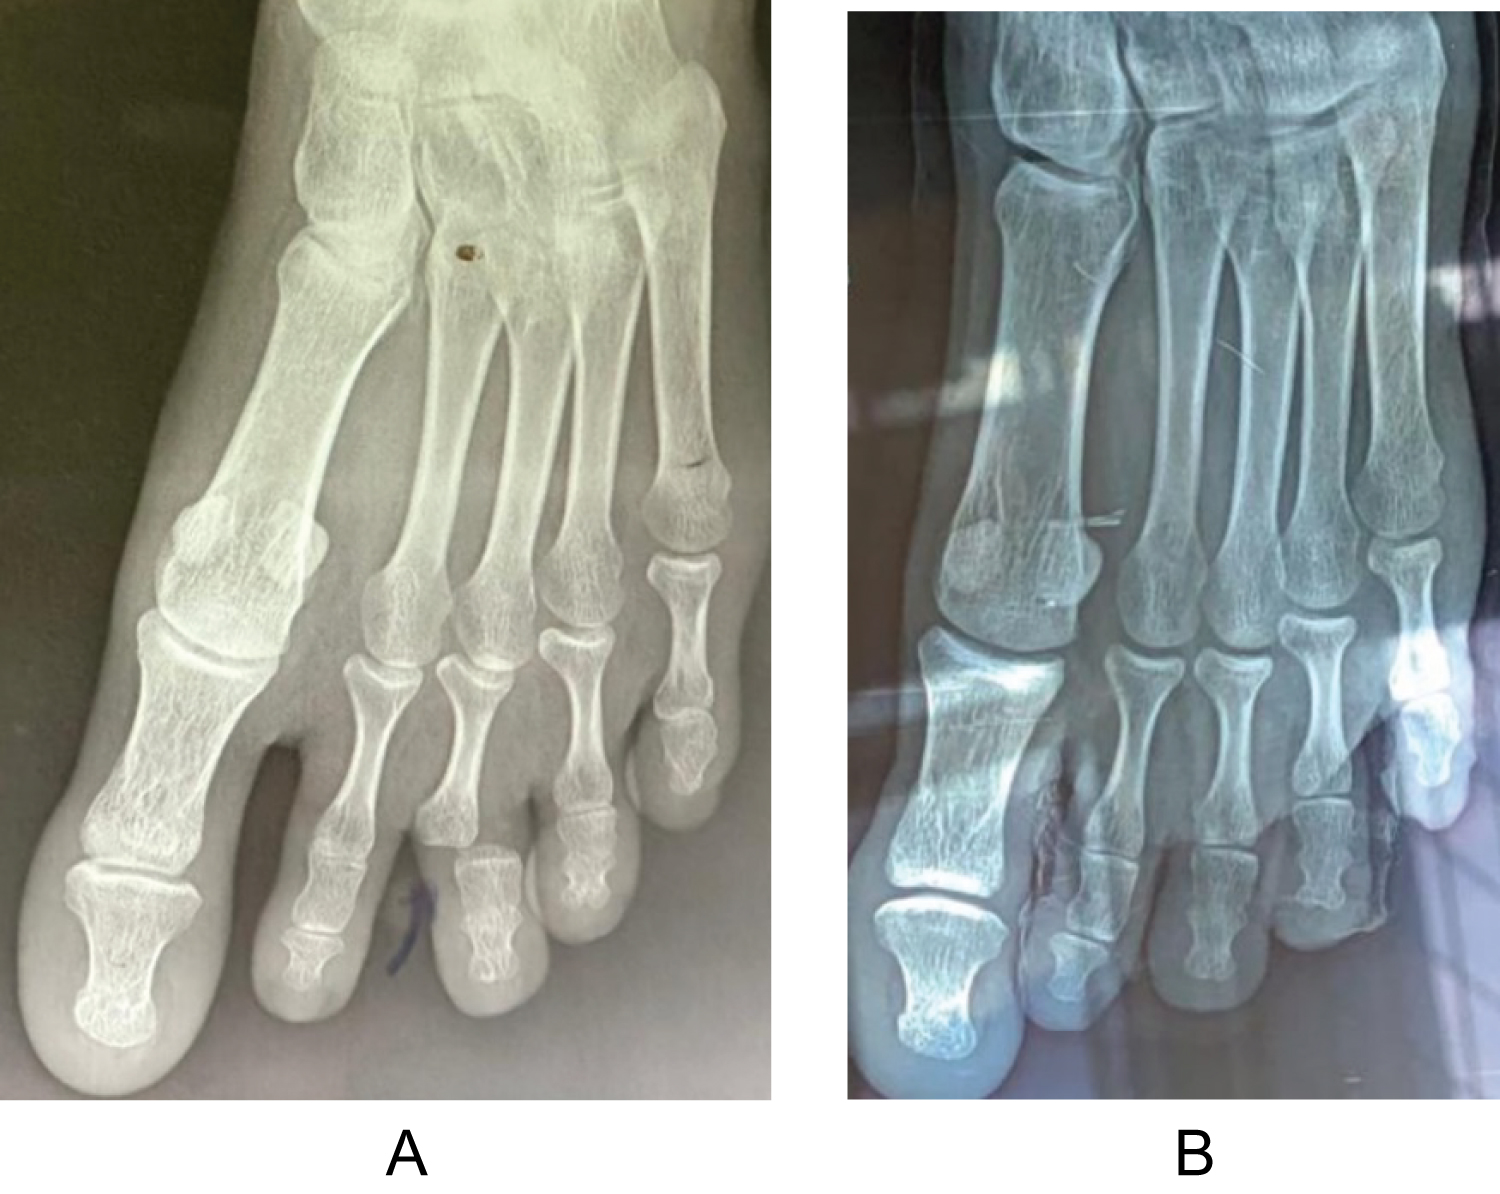

The patient was allowed to walk the day after the operation. Thromboembolic prevention was not necessary. Dressings were made every two days until complete healing. The stitchs were removed after two weeks. The plaster splint was permanently removed after four to six weeks. The rehabilitation sessions began the day after the final removal of the splint. Total return to work was possible in the second month after the operation. The patients were reviewed and examined once a month with X-ray control during the first three months postoperatively (Figure 4). The minimum follow-up period was six months.

Figure 4: (a) X-ray images of the lesion and; (b) At eight weeks post-operatively. View Figure 4